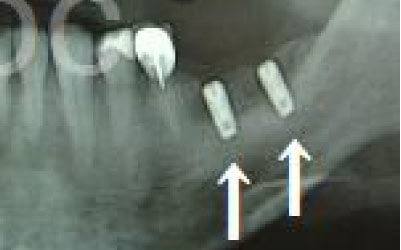

今回のご質問ですが、抜けた部分の骨が薄いなどの理由で「インプラントはできない」と言われた可能性があります。

前歯はもともと骨が薄く、歯が抜けると時間の経過とともにさらに骨が痩せてきてしまうので、インプラント治療の難易度が高い場所です。

ただ結論からお話すると、インプラント治療は可能です。

なぜなら、もし仮に骨が薄くても、骨の治療によって厚みが増せば、安全にインプラント治療が行えるからです。

なお、前歯のインプラント治療をご希望の方には、注意していただきたい点が4つほどあります。

1)インプラント治療を行う前に、骨の治療が必要かもしれません。

2)骨の治療から始めると、その分、治療期間が長くなります。

3)骨の治療は、通常のインプラント治療よりも難易度が高いため、経験の豊富な先生やインプラント認定医のいる歯科医院で治療を受けることをお勧めします。

4)骨の状況をしっかり把握するためにも、CT撮影が必須となります。

また、インプラント治療においては、周囲の歯の状況や咬み合わせの問題などもしっかりと考えて治療するのがとても大切です。

そのため、残っている歯についてもきちんと診査してくれるクリニックが良いでしょう。